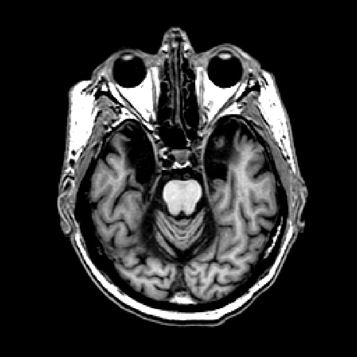

Offenbar hatte Karl Lashley bei seinen Studien am falschen Ort gesucht. In seinen Rattenexperimenten hatte er stets Teile der Hirnrinde, also der äußersten Schicht des Gehirns entfernt. Dieses Hirnareal ist in der Entwicklungsgeschichte des Gehirns das jüngste, alle anderen hielt Lashley für zu primitiv. H.M. fehlte es aber nicht an Hirnrinde, Scoville hatte einen Teil des Mandelkerns, der Amygdala, entfernt und fast den gesamten Hippocampus. Diese Region an der Innenseite der Schläfenlappen war offenbar entscheidend für das Formen neuer Erinnerungen.

Eine weitere Merkwürdigkeit im Fall H.M: Ihm fehlte zwar das Langzeitgedächtnis, aber für ein paar Sekunden konnte er sich alles merken. Viele Versuche haben gezeigt, dass sein Kurzzeitgedächtnis in etwa so gut funktionierte wie das eines gesunden Menschen. Telefonnummern oder Wortlisten etwa konnte H.M. sich kurze Zeit merken, wurde er aber nach ein paar Minuten oder Stunden noch einmal gefragt, hatte er sie vergessen. „H.M. war der Paradefall, der gezeigt hat, dass der Hippocampus zentral ist für die Übertragung vom Kurzzeit– ins Langzeitgedächtnis“, sagt Markowitsch. Was auf lange Zeit abrufbar bleiben soll, das muss offenbar durch das Nadelöhr des Hippocampus. So haben Forscher mit bildgebenden Verfahren gezeigt, dass sich Menschen aus einer Liste von Wörtern an die am besten erinnern, bei deren Lernen der Hippocampus am stärksten aktiv war.

Der Hippocampus ist der größte Teil des Archicortex und ein Areal im Temporallappen. Er ist zudem ein wichtiger Teil des limbischen Systems. Funktional ist er an Gedächtnisprozessen, aber auch an räumlicher Orientierung beteiligt. Er umfasst das Subiculum, den Gyrus dentatus und das Ammonshorn mit seinen vier Feldern CA1-CA4.